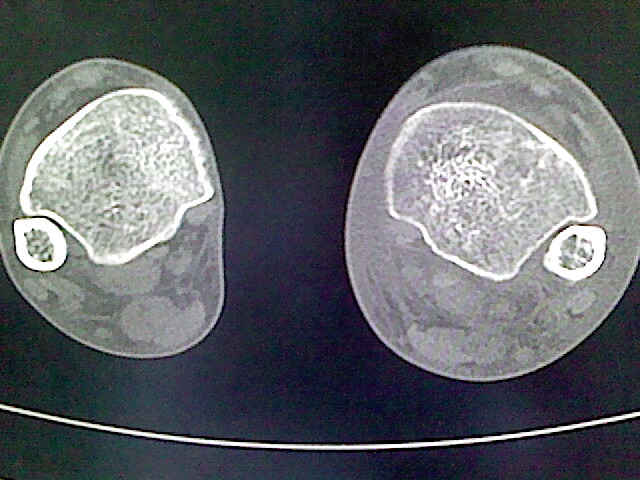

男,76岁,左小腿疼痛,不能站立

本例骨质改变主要表现为滑膜或韧带区的骨侵蚀融解(胫腓联合区骨质破坏无硬化边),距骨后部骨质破坏区有硬化边及死骨样改变.所以,本例考虑关节结核可能性大,绒毛膜结节性滑膜炎多发于中年,且极少见于膝髋以外的关节,骨质硬坏也以压陷吸收为主,有明显的硬化边,骨膜增生呈结节状(可以mr鉴别),所以本例暂除外.

另不除外可引起相似表现的其他炎症如布氏杆菌性关节炎等